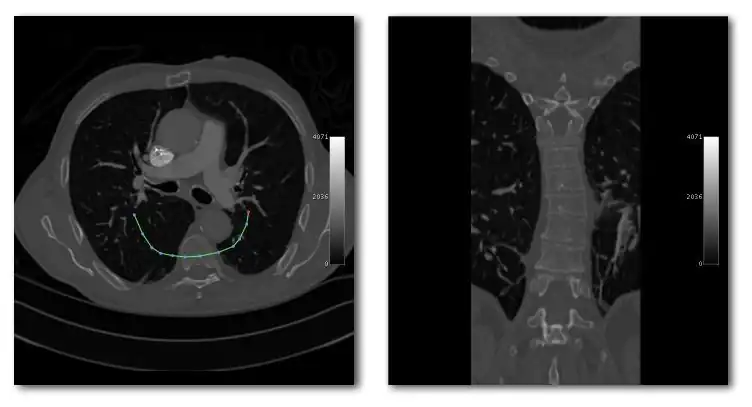

- Curved Reconstruction

- Curved MPRs can be used for the reconstruction of more complex perspectives, as illustrated in Figure 5.21.

- Here a curve (highlighted in green) can been positioned in the axial images (left panel) to define a curved surface which extends through the voxel data in the z-direction, and voxels from this data can be reconstructed into a two-dimensional image (right panel). Note that more complex curves than the one illustrated can be generated so that, for instance, the three-dimensional course of a major blood vessel can be isolated, or CT head scans can be planarized for orthodontic applications.